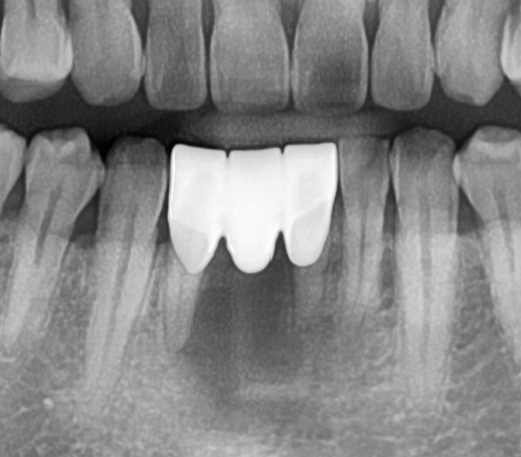

브릿지 치료 후 엑스레이